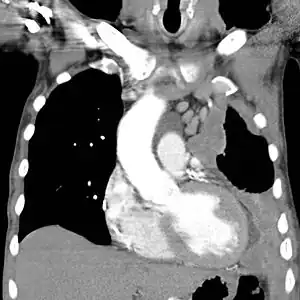

CT scan showing a left sided mesothelioma with an enlarged mediastinal lymph node

CT scan of a patient with mesothelioma, coronal section (the section follows the plane that divides the body in a front and a back half). The mesothelioma is indicated by yellow arrows, the central pleural effusion (fluid collection) is marked with a yellow star. Red numbers: (1) right lung, (2) spine, (3) left lung, (4) ribs, (5) descending part of the aorta, (6) spleen, (7) left kidney, (8) right kidney, (9) liver.